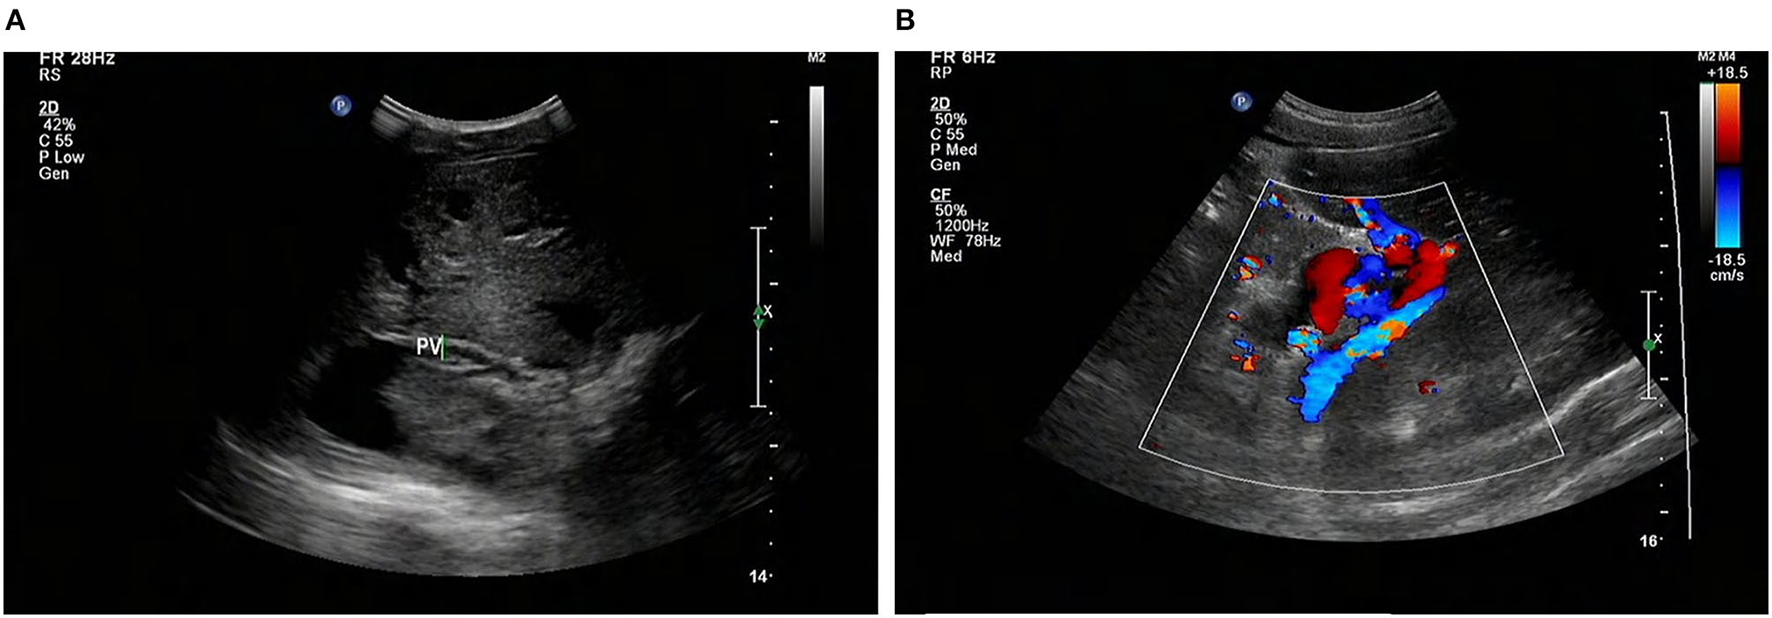

At that moment, an amazing discovery was found by abdominal ultrasonography (US): his intrahepatic portal vein (PV) was absent, which seemed to be occluded (Figure 2A). To better understand this anatomic anomaly, we performed additional portal computed tomography angiography (CTA). It consistently delineated the dysplasia of the portal vein. There seemed to be two pathways for blood to flow in the main splenic vein (SV): one was in the portal vein that merged with the superior mesenteric vein and sent out a small branch into the liver (Figures 3A,B), whilst the other entered the inferior vena cava (IVC) via left renal vein. Also worth noting is that the hepatic artery was widened. Some regenerative nodules and abnormal hyperplasia nodules were visible. Liver magnetic resonance imaging (MRI) confirmed their existence (Figure 4).

FIGURE 2

www.frontiersin.org

Figure 2. Abdominal US shows that the intrahepatic PV system is absent (arrows) (A), and the GDV is tortuous and dilated (B). US, ultrasonography; PV, portal vein; GDV, gastric fundus vein; STO: stomach.

AM is a congenital vascular malformation in the liver. Imaging shows that SMV and SV were fused in this patient and partially injected into the left renal vein, and there was a small portal vein running through the liver (Figures 2, 3). According to the classification proposed by Morgan and Superina (2), these features are classified as AM type II. To the best of our knowledge, AM rarely presents with syncope, and our patient is the first case of a male with CEPS (Abernethy II) showing syncope.